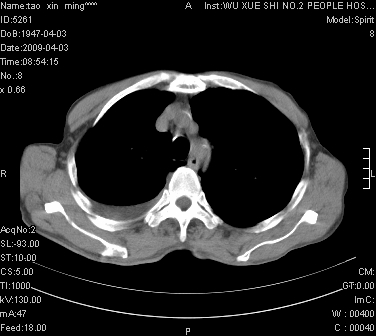

男.62.咯血.胸痛

是不是外伤的,看起来右侧肋骨骨折,右肺唑伤,右胸腔积血, 右肺背段可见一软组织肿块,边缘清晰,可以和中中央型肺ca合并

明天请武大中南医院外科熊主任手术.患者无外伤.我考虑肺癌

1)考虑右肺下叶周围型肺癌,并右肺下叶肺出血。2)右侧少量胸腔积液。

1)考虑右肺下叶周围型肺癌。2)右侧少量胸腔积液。